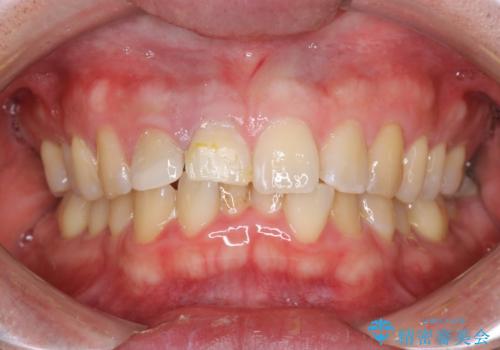

PMTCで歯の着色落とし

- 歯の着色・汚れが気になるとのことでクリーニンング希望とのことでした。PMTC30分コースを行いました。

プラーク(細菌の塊)や歯石がたまると歯の表面はザラつきいてきます。そのザラつきは歯周病や虫歯菌の棲家となります。そのまま放置すると、歯肉が腫れてきたり、歯肉から出血したり、口臭が強くでたりします。とくに歯肉の境目は、歯磨きで汚れを除去することが難しく、プラーク(細菌の塊)や歯石が溜まりやすい場所です。

歯並が、がたついている場合はなおさら汚れが溜まりやすいです。矯正治療前や定期的にPMTCをすることで、歯肉トラブルを防ぐことにつながります。